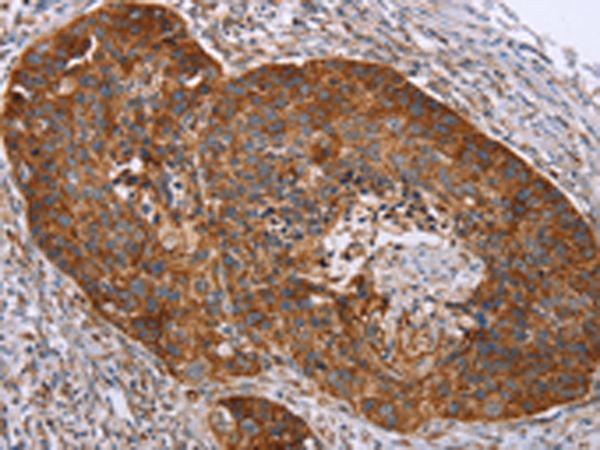

分类: 科研抗体货号: P01654别名: P2; MP2; FABP8; M-FABP应用: WB,IHC反应种属: Human, Mouse